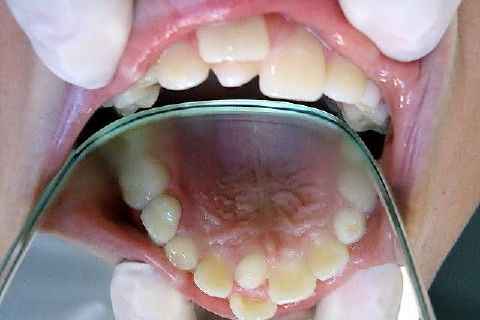

Hiperdontia: Supranumerário na Região Palatina do Dente 11

Ao exame clínico, constatei a presença de um supranumerário na região palatina do dente 11, que se encontrava deslocado para vestibular.

A presença desses dentes pode causar problemas, como falhas na erupção, deslocamento de dentes, apinhamentos, cistos e tumores odontogênicos.

Fotos do caso